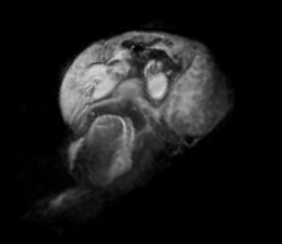

Courtesy of Kurniawan ND, University of Queensland

磁気共鳴顕微鏡は、病院のMRI装置で日常的に使用されている技術で、0.5~66 mmの小さなサンプルを10×10×10 μm3(1ピコリットル)の分解能でイメージングすることに注力しています。この分解能は、市場をリードするブルカーの垂直ボア(スタンダードからスーパーワイドボア)の高磁場磁気共鳴システムと最先端のイメージングアクセサリーを組み合わせることで達成されます。